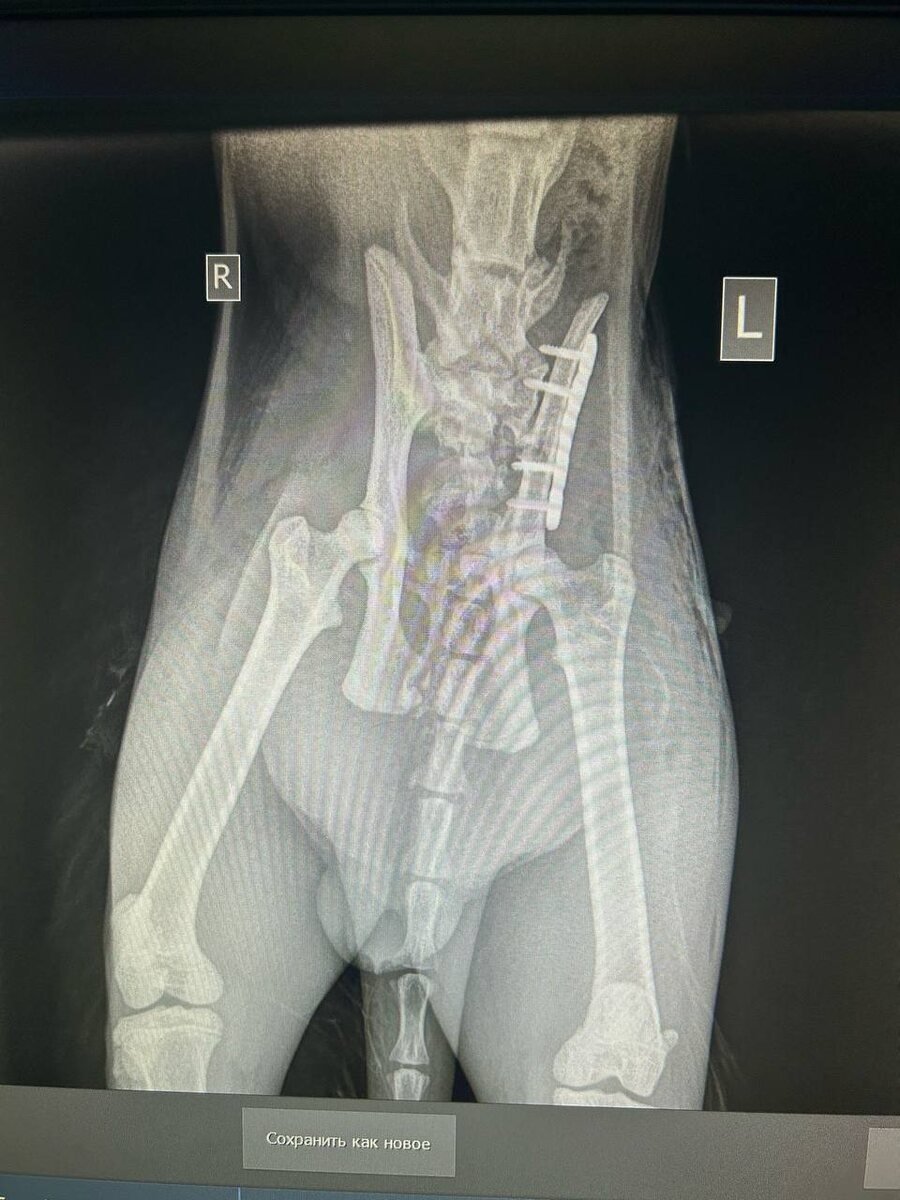

Рыжего Аполлона прооперировали!

Собрали таз, поставили пластину!